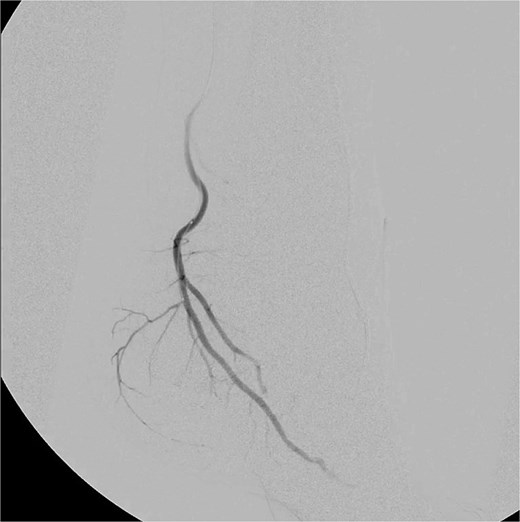

Selective catheterization of the target branch was performed using a 0.014-inch guidewire and microcatheter, followed by embolization with Imipenem–Cilastatin (2 mL) (Fig. 2). The vascular blush resolved completely, confirming procedural success. Hemostasis was achieved using a Safeguard compression device, with blood loss <30 mL and procedure time < 15 minutes. The total contrast used was 7 mL (Omnipaque, 200–299 mg I/mL).

Selective catheterization and targeted embolization of the hypervascular branches of the left medial plantar artery using imipenem–Cilastatin (2 mL) as the embolic agent, demonstrating successful occlusion of abnormal vascularity on post-embolization angiography.